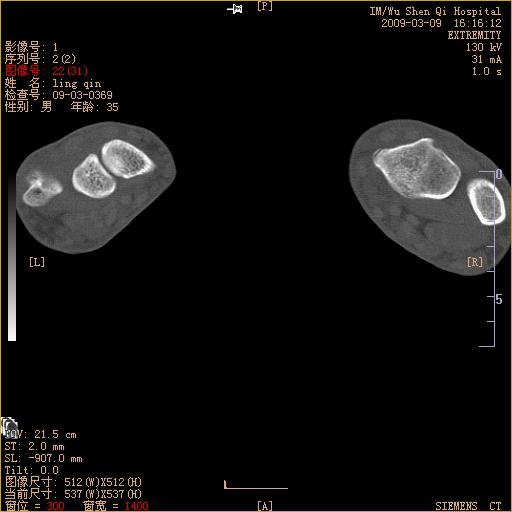

标题: CT18570:右手外伤10余天 [打印本页]

标题: CT18570:右手外伤10余天

腕部有骨折、脱位,骨科面对ct片如何采取措施?三维一下。

舟状骨骨折。

左侧舟骨及桡骨茎突骨折,第一掌骨基底部好像也有骨折,建议上传平片